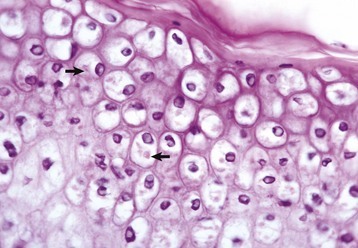

Describe this finding. What is it associated with?

This is balooning degeneration.

Viral.